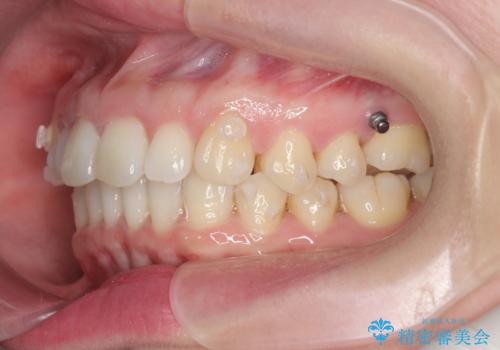

インビザライン で治す 出っ歯の治療

- 前歯の突出感、出っ歯の治療を希望され来院されました。

インビザラインを用いた治療計画を立て、しっかりと出っ歯を治すためにマイクロインプラントを併用します。

マイクロインプラントを併用することでしっかりとマウスピース全体を後方へ引き、前歯の突出感を改善することができました。